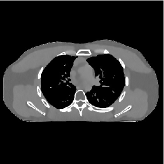

This section compares the reconstruction quality and runtime among the proposed MBIR method, PWLS-ST-, and other three MBIR methods, PWLS-EP, PWLS-DL, and PWLS-ST-. Table I shows that, for both 2D and 3D sparse-view CT reconstructions of the XCAT phantom, the proposed PWLS-ST- model outperforms PWLS-EP and PWLS-ST- in terms of RMSE. In addition, PWLS-ST- using a square transform (of size ) achieves lower RMSE than PWLS-DL using an overcomplete dictionary (of size ) for 2D sparse-view reconstructions. Fig. 3(a) and Fig. 4 show the reconstructed images for 2D and 3D phantom experiments, with different reconstruction models and different number of views. (See the corresponding error maps in the supplement.) The proposed PWLS-ST- consistently gives more accurate image reconstructions compared to other MBIR methods. Specifically, PWLS-ST- has smaller errors in the heart region (see zoom-ins in Fig. 3(a)) of 2D reconstructions than PWLS-DL and PWLS-ST-. In addition, compared to PWLS-ST-, PWLS-DL and PWLS-ST- have some ringing artifacts around the edges with high transition, e.g., edges between air and soft tissues. (See a comparison of profiles of PWLS-ST- and PWLS-ST- in the supplement.) In particular, PWLS-ST- and PWLS-DL give more visible ringing artifacts for 2D reconstruction from fewer views, and PWLS-ST- has these ringing artifacts for 3D reconstructions regardless of the number of views (see zoom-ins in Fig. 4). Table II reports runtimes of different MBIR methods in reconstructing the -views XCAT phantom scan. (FBPConvNet is a non-MBIR method and its runtime for processing a image is approximately one second with a TITAN Xp GPU.) While providing better reconstruction quality, the proposed Algorithm 1 of PWLS-ST- has shorter runtime compared to the algorithms of PWLS-DL and PWLS-ST- in Section III-A. Similar to the PWLS-EP algorithm, the reconstruction time of the PWLS-DL, PWLS-ST-, and PWLS-ST- algorithms can be further reduced by using ordered subsets [51].

| (b) 3D axial cone-beam CT experiments |

This section compares the generalization capabilities between the proposed MBIR method, PWLS-ST-, and a denoising deep NN, FBPConvNet [14], that are trained from the phantom data; in particular, we tested the trained PWLS-ST- and FBPConvNet models to phantom and clinical scan data. The results in Fig. 6 show that the non-MBIR FBPConvNet method has higher overfitting risks, compared to the proposed PWLS-ST- MBIR method. When tested on clinical scan data, PWLS-ST- achieves much more accurate reconstruction, compared to FBPConvNet. See Fig. 6(b). When tested on phantom data, FBPConvNet generates more unnatural features as the number of views reduces, although it gives lower RMSE values compared to PWLS-ST-. See zoom-ins in Fig. 6(a). The FBPConvNet results above correspond to those in the recent work [16] that FBPConvNet [14] generated some unexpected structures.